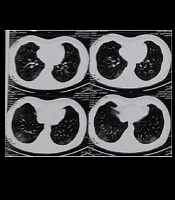

Advanced Gastric Adenocarcinoma in a 12-Year-Old Girl

Ghasem Miri-AliabadORCID*,

Leila Asgarzadeh ORCID,

Abasali NiaziORCID